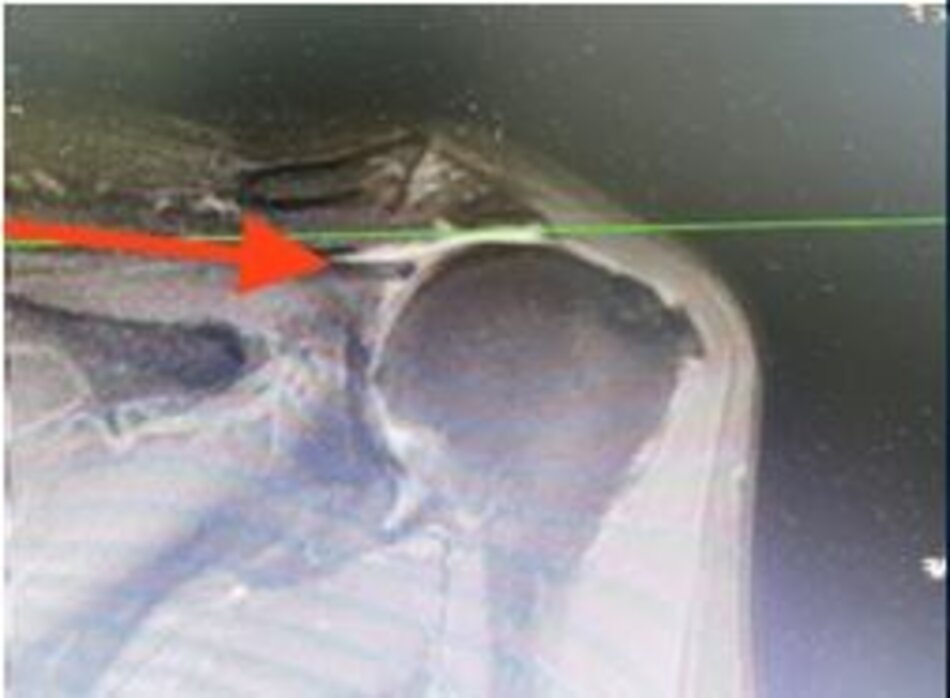

Rách gân trên gai trên phim chụp cộng hưởng từ và hình ảnh tương ứng qua nội soi khớp vai

Gân trên gai sau khi được tạo hình khâu lại vào điểm bám cũ

Hình ảnh cộng hưởng từ sau mổ 6 tháng